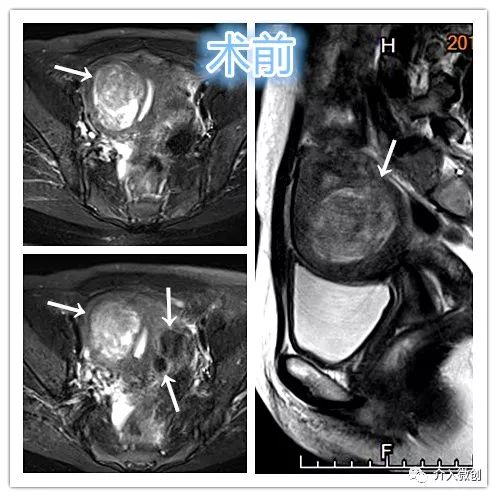

中年妇女,因子宫肌瘤导致长期的月经量明显增多、经期延长,最终导致严重贫血。

- MRI检查显示子宫多发肌瘤。

MRI检查示肌壁间型子宫肌瘤

术前子宫MRI

- 对比术后6个月复查MRI显示肌瘤已明显缩小,月经量已回复正常,生活质量明显改善。

术后6个月复查子宫MRI